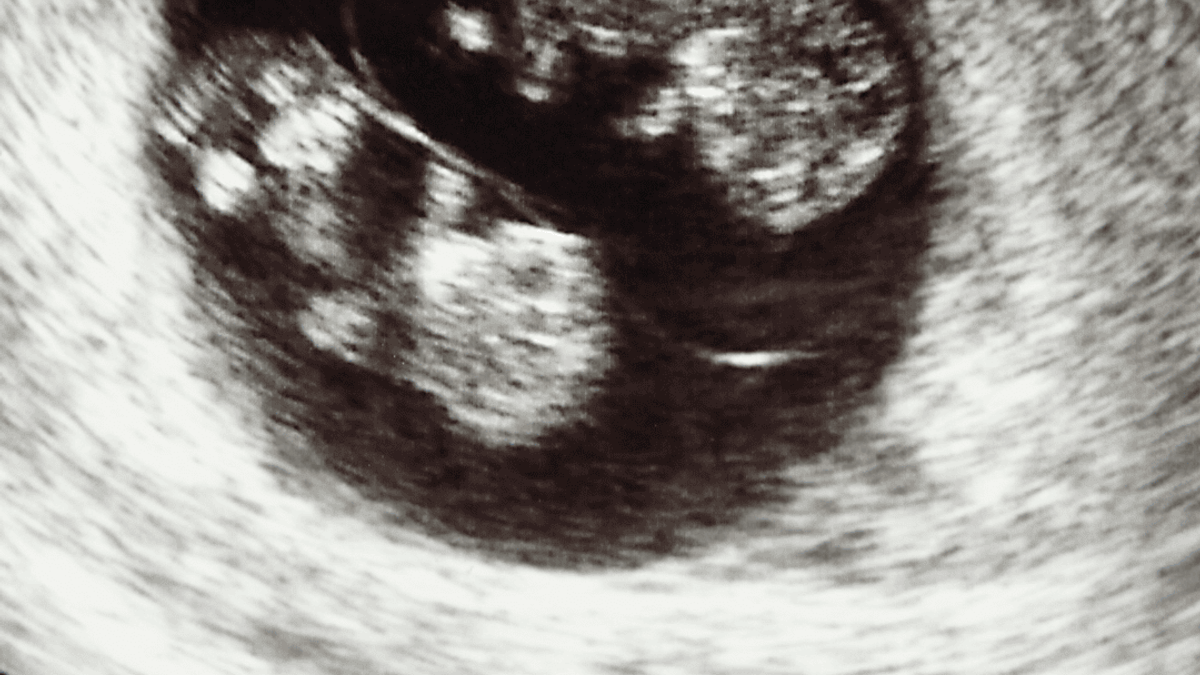

“Fabienne?” hoorde ik een stem. Het was de verloskundige. Ze stelde zich voor, vroeg hoe ik me voelde en leidde ons naar de kamer waar de echo gemaakt zou worden. “Voor de duidelijkheid doen we een inwendige echo,” legde ze uit. “Dan kunnen we het beter zien.” Ik knikte, voelde een lichte spanning door mijn lichaam gaan, maar concentreerde me op de monitor. “Kijk,” zei ze na een paar seconden. “Hier is een kloppend hartje.” Ik voelde een golf van opluchting en geluk. Pepijn keek me aan met tranen in zijn ogen. We zagen ons kindje! Of ja, een klein stipje dat blijkbaar een kindje zou worden.

De verloskundige bewoog de echo iets heen en weer. “Even goed checken of het er echt één is,” mompelde ze. Pepijn en ik moesten lachen. “We zullen onze handen al vol hebben aan één,” zei hij plagend.

“Nou, ik zie hier toch echt twee kloppend hartjes”

De verloskundige keek ons ineens wat serieuzer aan. “Nou,” begon ze. “Ik zie hier toch echt twee kloppende hartjes.” Het was even stil. “Twee?” herhaalde ik, alsof ik het niet goed gehoord had. Ze draaide het scherm iets meer naar ons toe en wees. “Kijk, hier is het ene hartje, en hier is het andere.” Pepijn en ik keken elkaar aan. Zijn ogen waren groot van verbazing. “We krijgen een tweeling?” vroeg hij zacht.